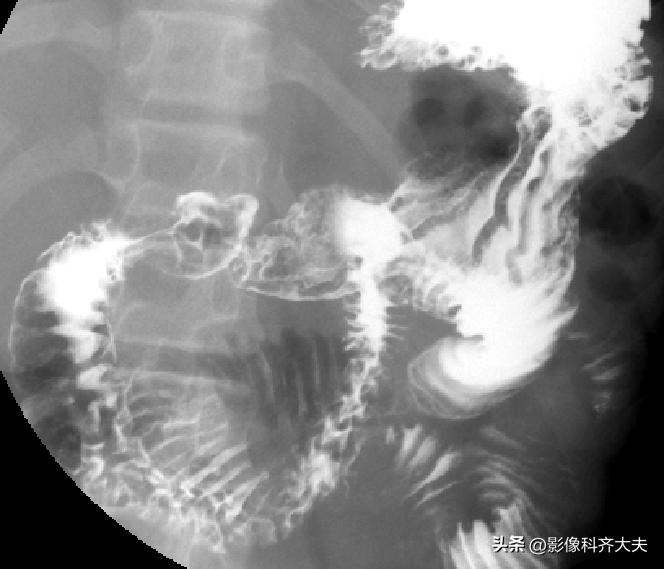

十二指肠球和圈充盈相

十二指肠球和圈双对比相

十二指肠球部及胃窦部加压相

全胃充盈相(站立位)